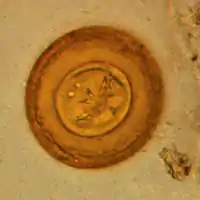

La oncosfera o hexacanto es un estado larvario de los cestodos. Esta larva es ciliada, esférica, y está provista de tres pares de ganchos; se encuentra contenida en la envoltura embrionaria externa del huevo.[1][2][3] Es el primer estado diferenciado en los ciclofilídeos. El conjunto de la oncosfera y el embrióforo se denomina coracidio.[4]